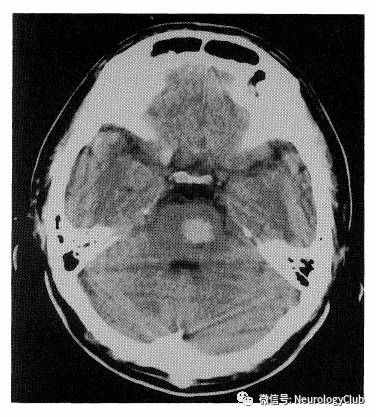

(图15:一例NBD患者,头颅CT可见急性出血)